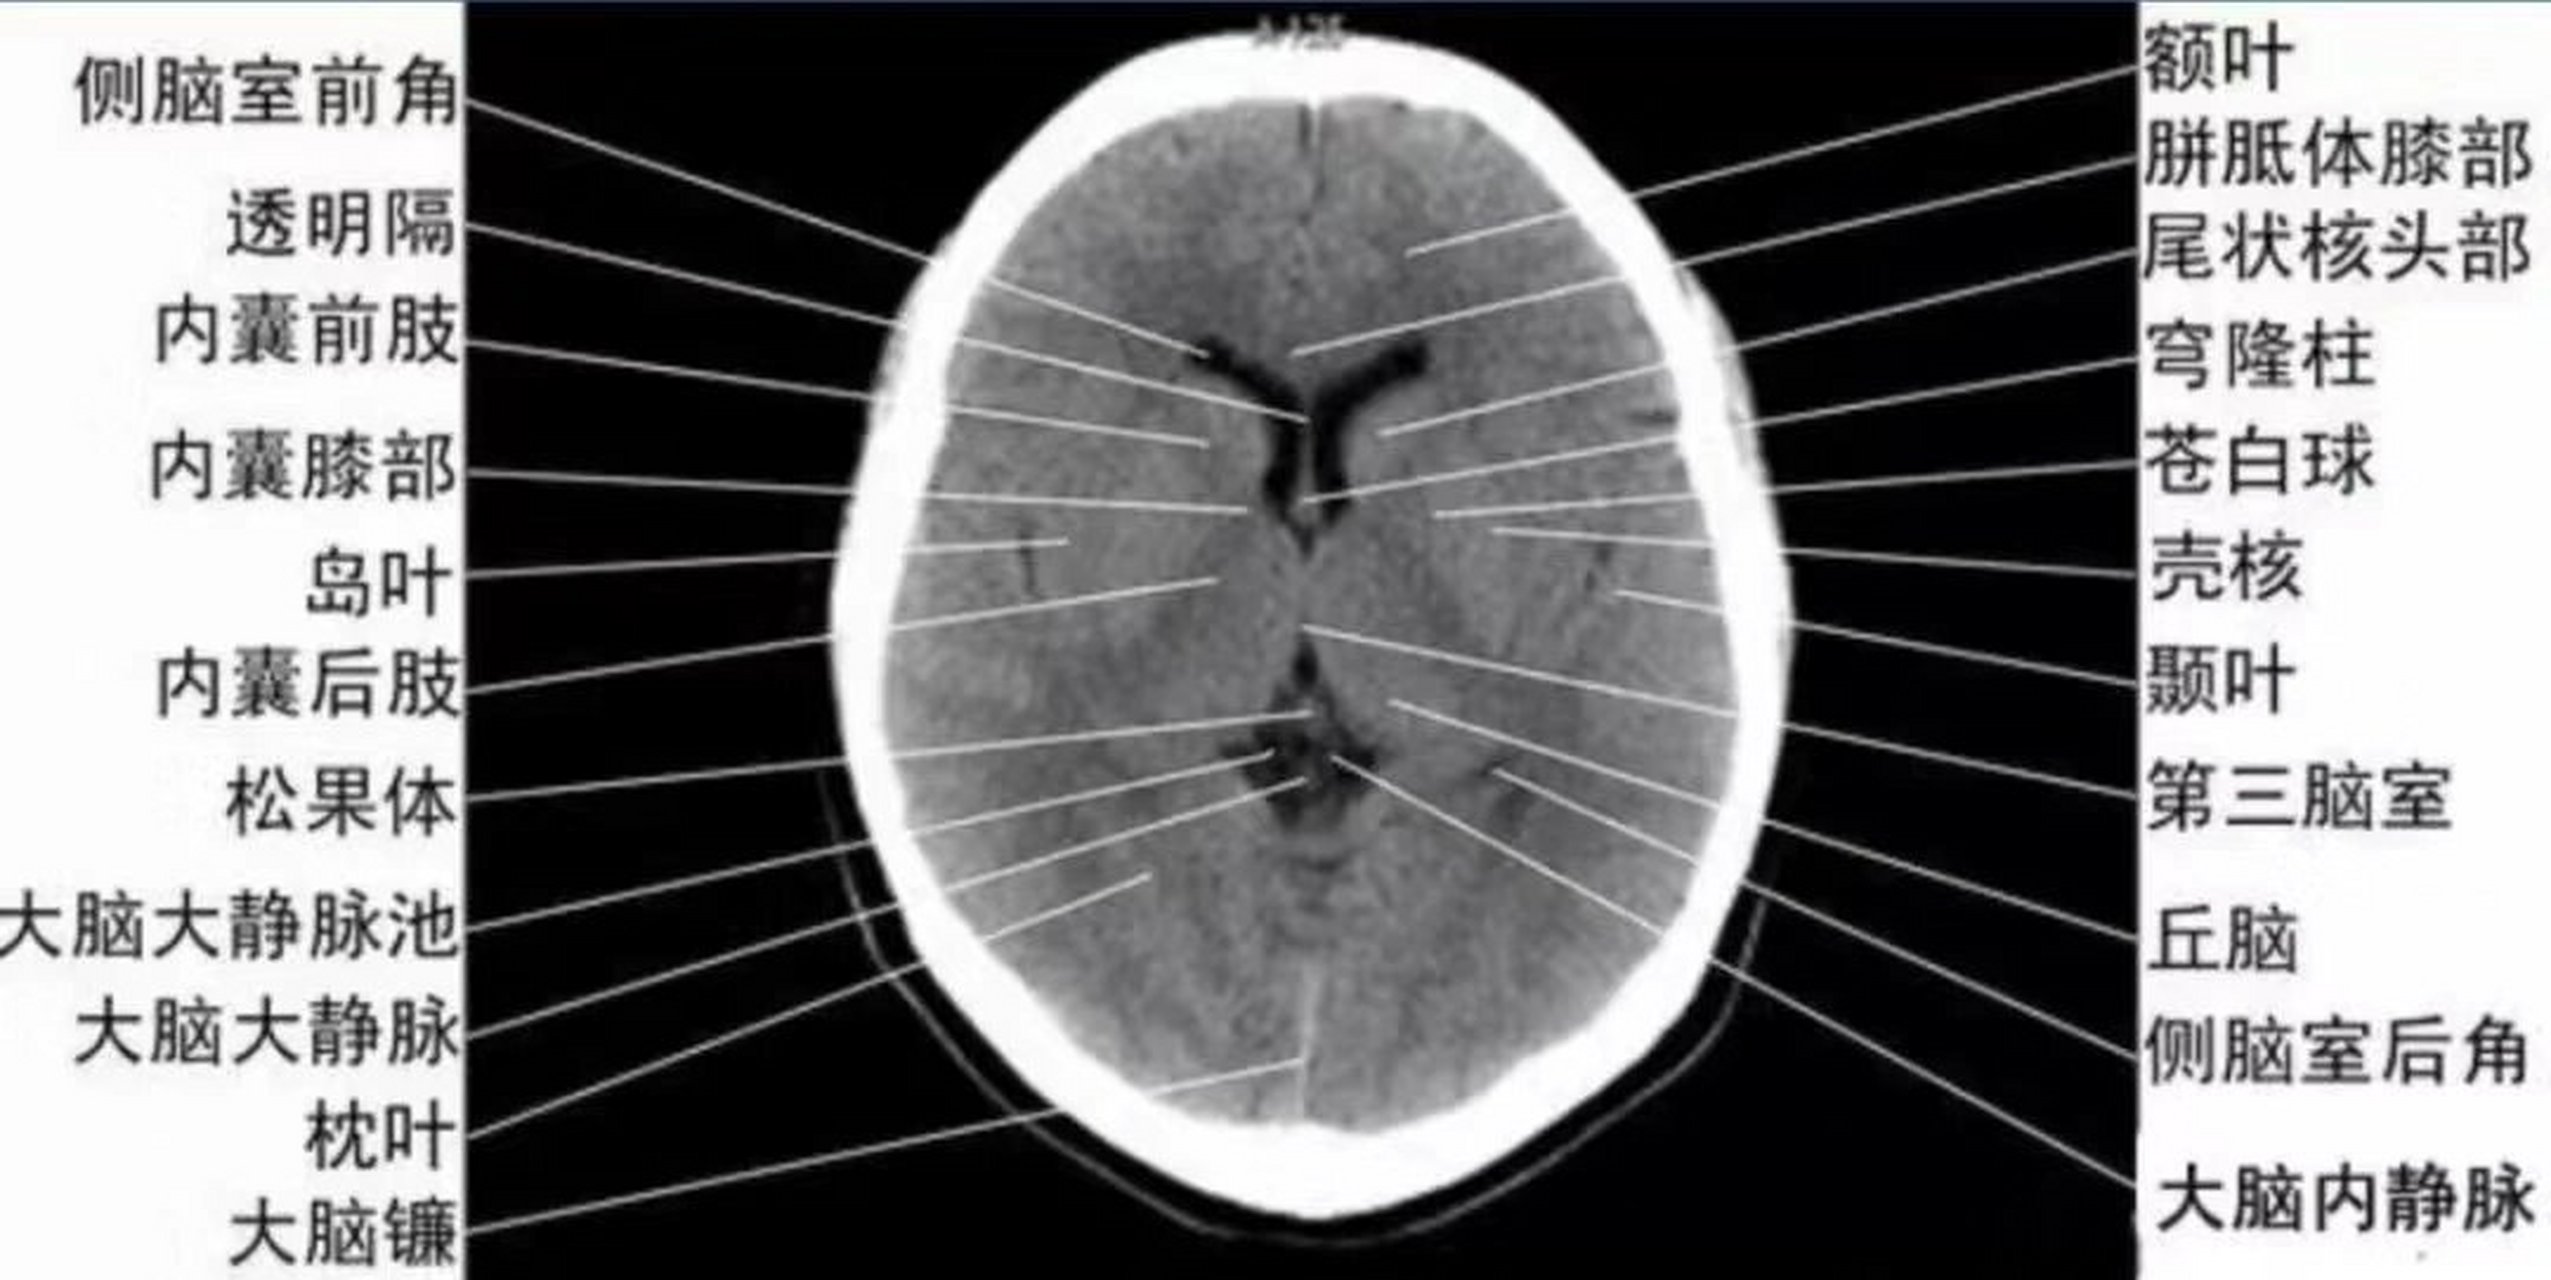

基底节区解剖与定位